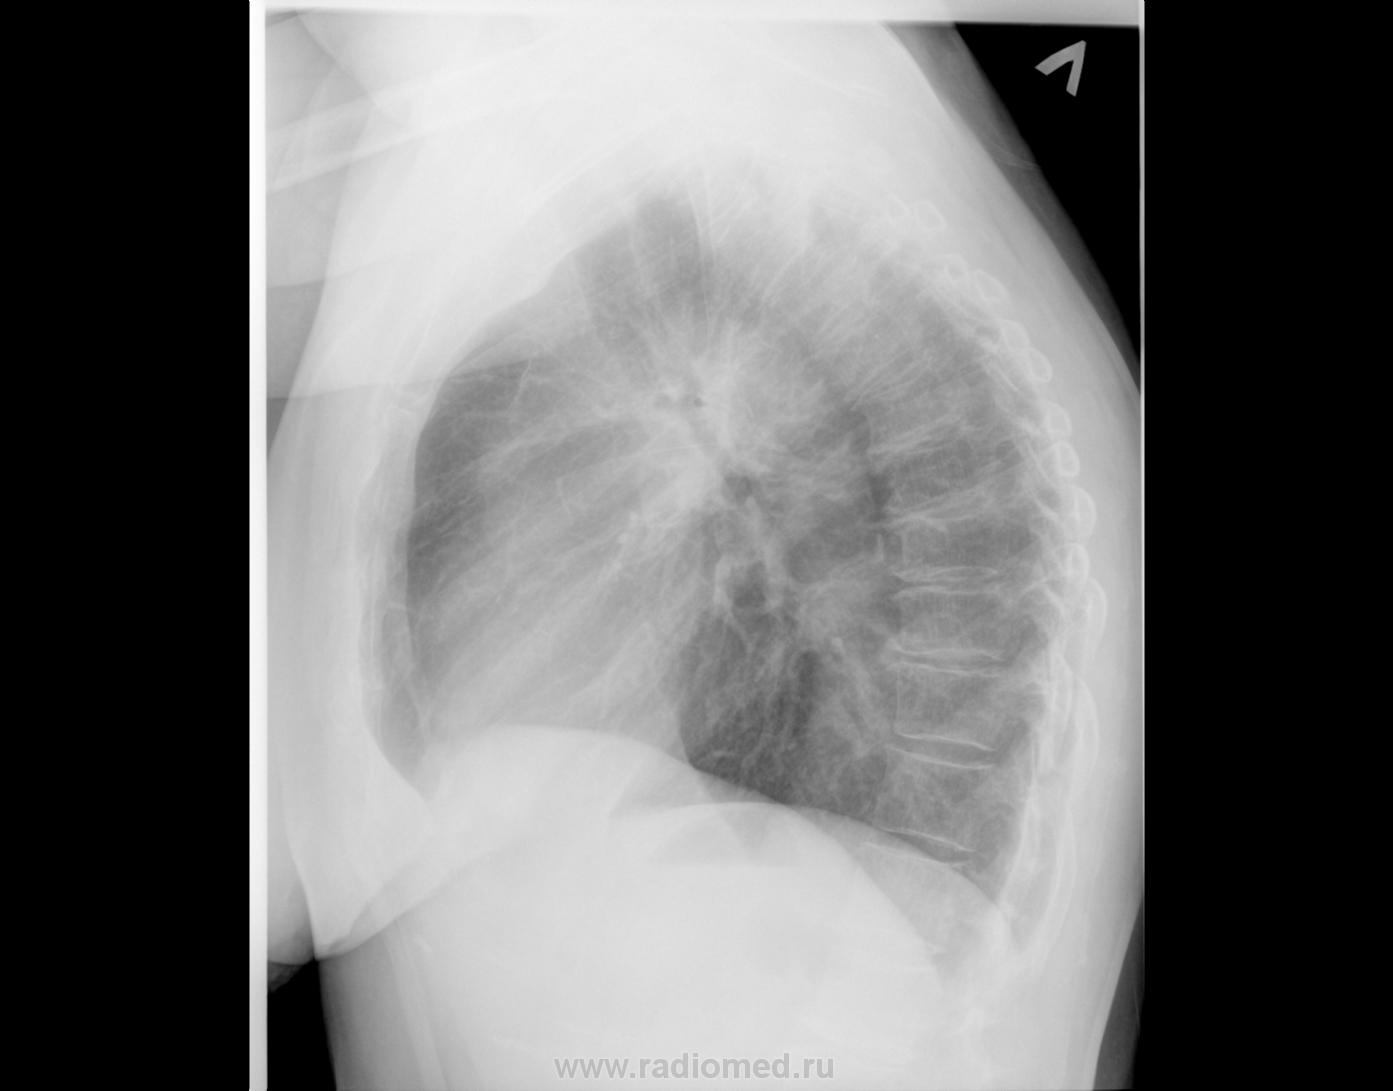

Пожилая пациентка, метастаз аденокарциномы в бедренную кость. Исследование выполнено с целью поиска первичного очага. Есть ли к чему придраться?

I-ое ребро слева вроде нехорошее.

1. Правому корню доверия нет.

2. Два позвонка грудного отдела не хило поротичны.

Слишком много лёгочного рисунка... хочется "натянуть" на карциноматоз. Плюсом первое ребро слева, согласна.

Глюк... 2 трахеи на боковом, а на прямом бифуркация очень странная, не видно главных... Пора спать))).

Ребро - ощущение остеолитического очага, рисунок - его очень много,  вроде и диссеминация, а вроде нет... Интерстициальная сетка видится.

Плотноват в области головки и тела, создается впечатление, что несколько подтянут.

Рискну и я: на первом снимке - нечеткая головка правого корня, правый корень поднятут кверху. На втором - плюс треугольная тень в верхне-медиальном отделе справа и очаговая тень на 2-м ребре справа. Предположу первичный очаг - центральный рак верхней доли правого легкого.